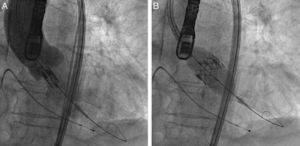

ProcedureThe procedure was performed under general anesthesia in a sterile environment in the hemodynamic laboratory, with patients being extubated in the same room in most cases. The Edwards SAPIEN aortic prosthesis consists of a trileaflet bovine pericardial prosthesis mounted on a balloon-expandable metal stent (Fig. 1). Two sizes are currently available: 23mm (for a valve annulus of 18–21.5mm) and 26mm (for a valve annulus of 21.5–25mm). A temporary pacemaker lead is positioned via the femoral vein in the right ventricle, and balloon aortic valvuloplasty is performed under rapid ventricular pacing (∼200bpm) following the standard technique. A retrograde approach is used as described previously.13 The sheath is introduced by sequential dilation of the access site from the femoral artery to the infrarenal aorta, and through this the balloon-mounted prosthesis is inserted. The system is advanced through the native valve and the balloon is inflated, again under rapid pacing, to expand the stent and implant it in the native valve annulus, compressing the valve leaflets (Fig. 2). The procedure is monitored by angiography and three-dimensional transesophageal echocardiography. The antiplatelet therapy prescribed for most patients was aspirin 100mg/day and clopidogrel 75mg/day for three months.